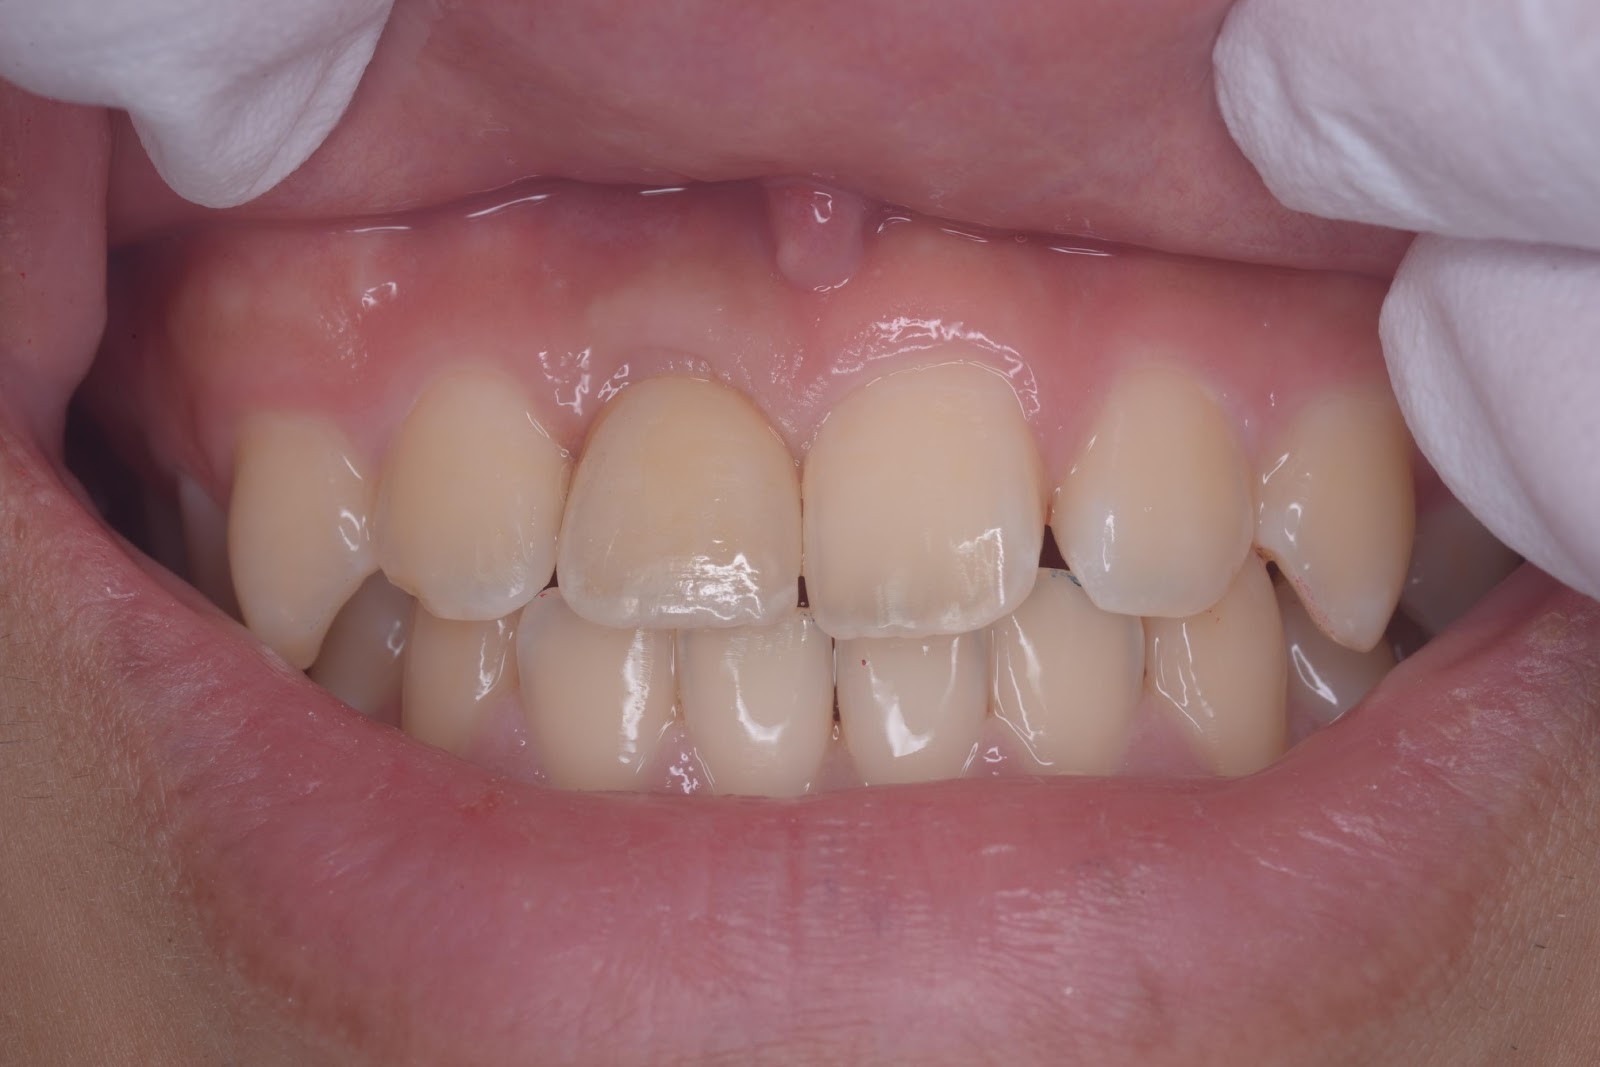

インプラント埋入

50代 女性

40代 女性

20代 男性

60代 男性